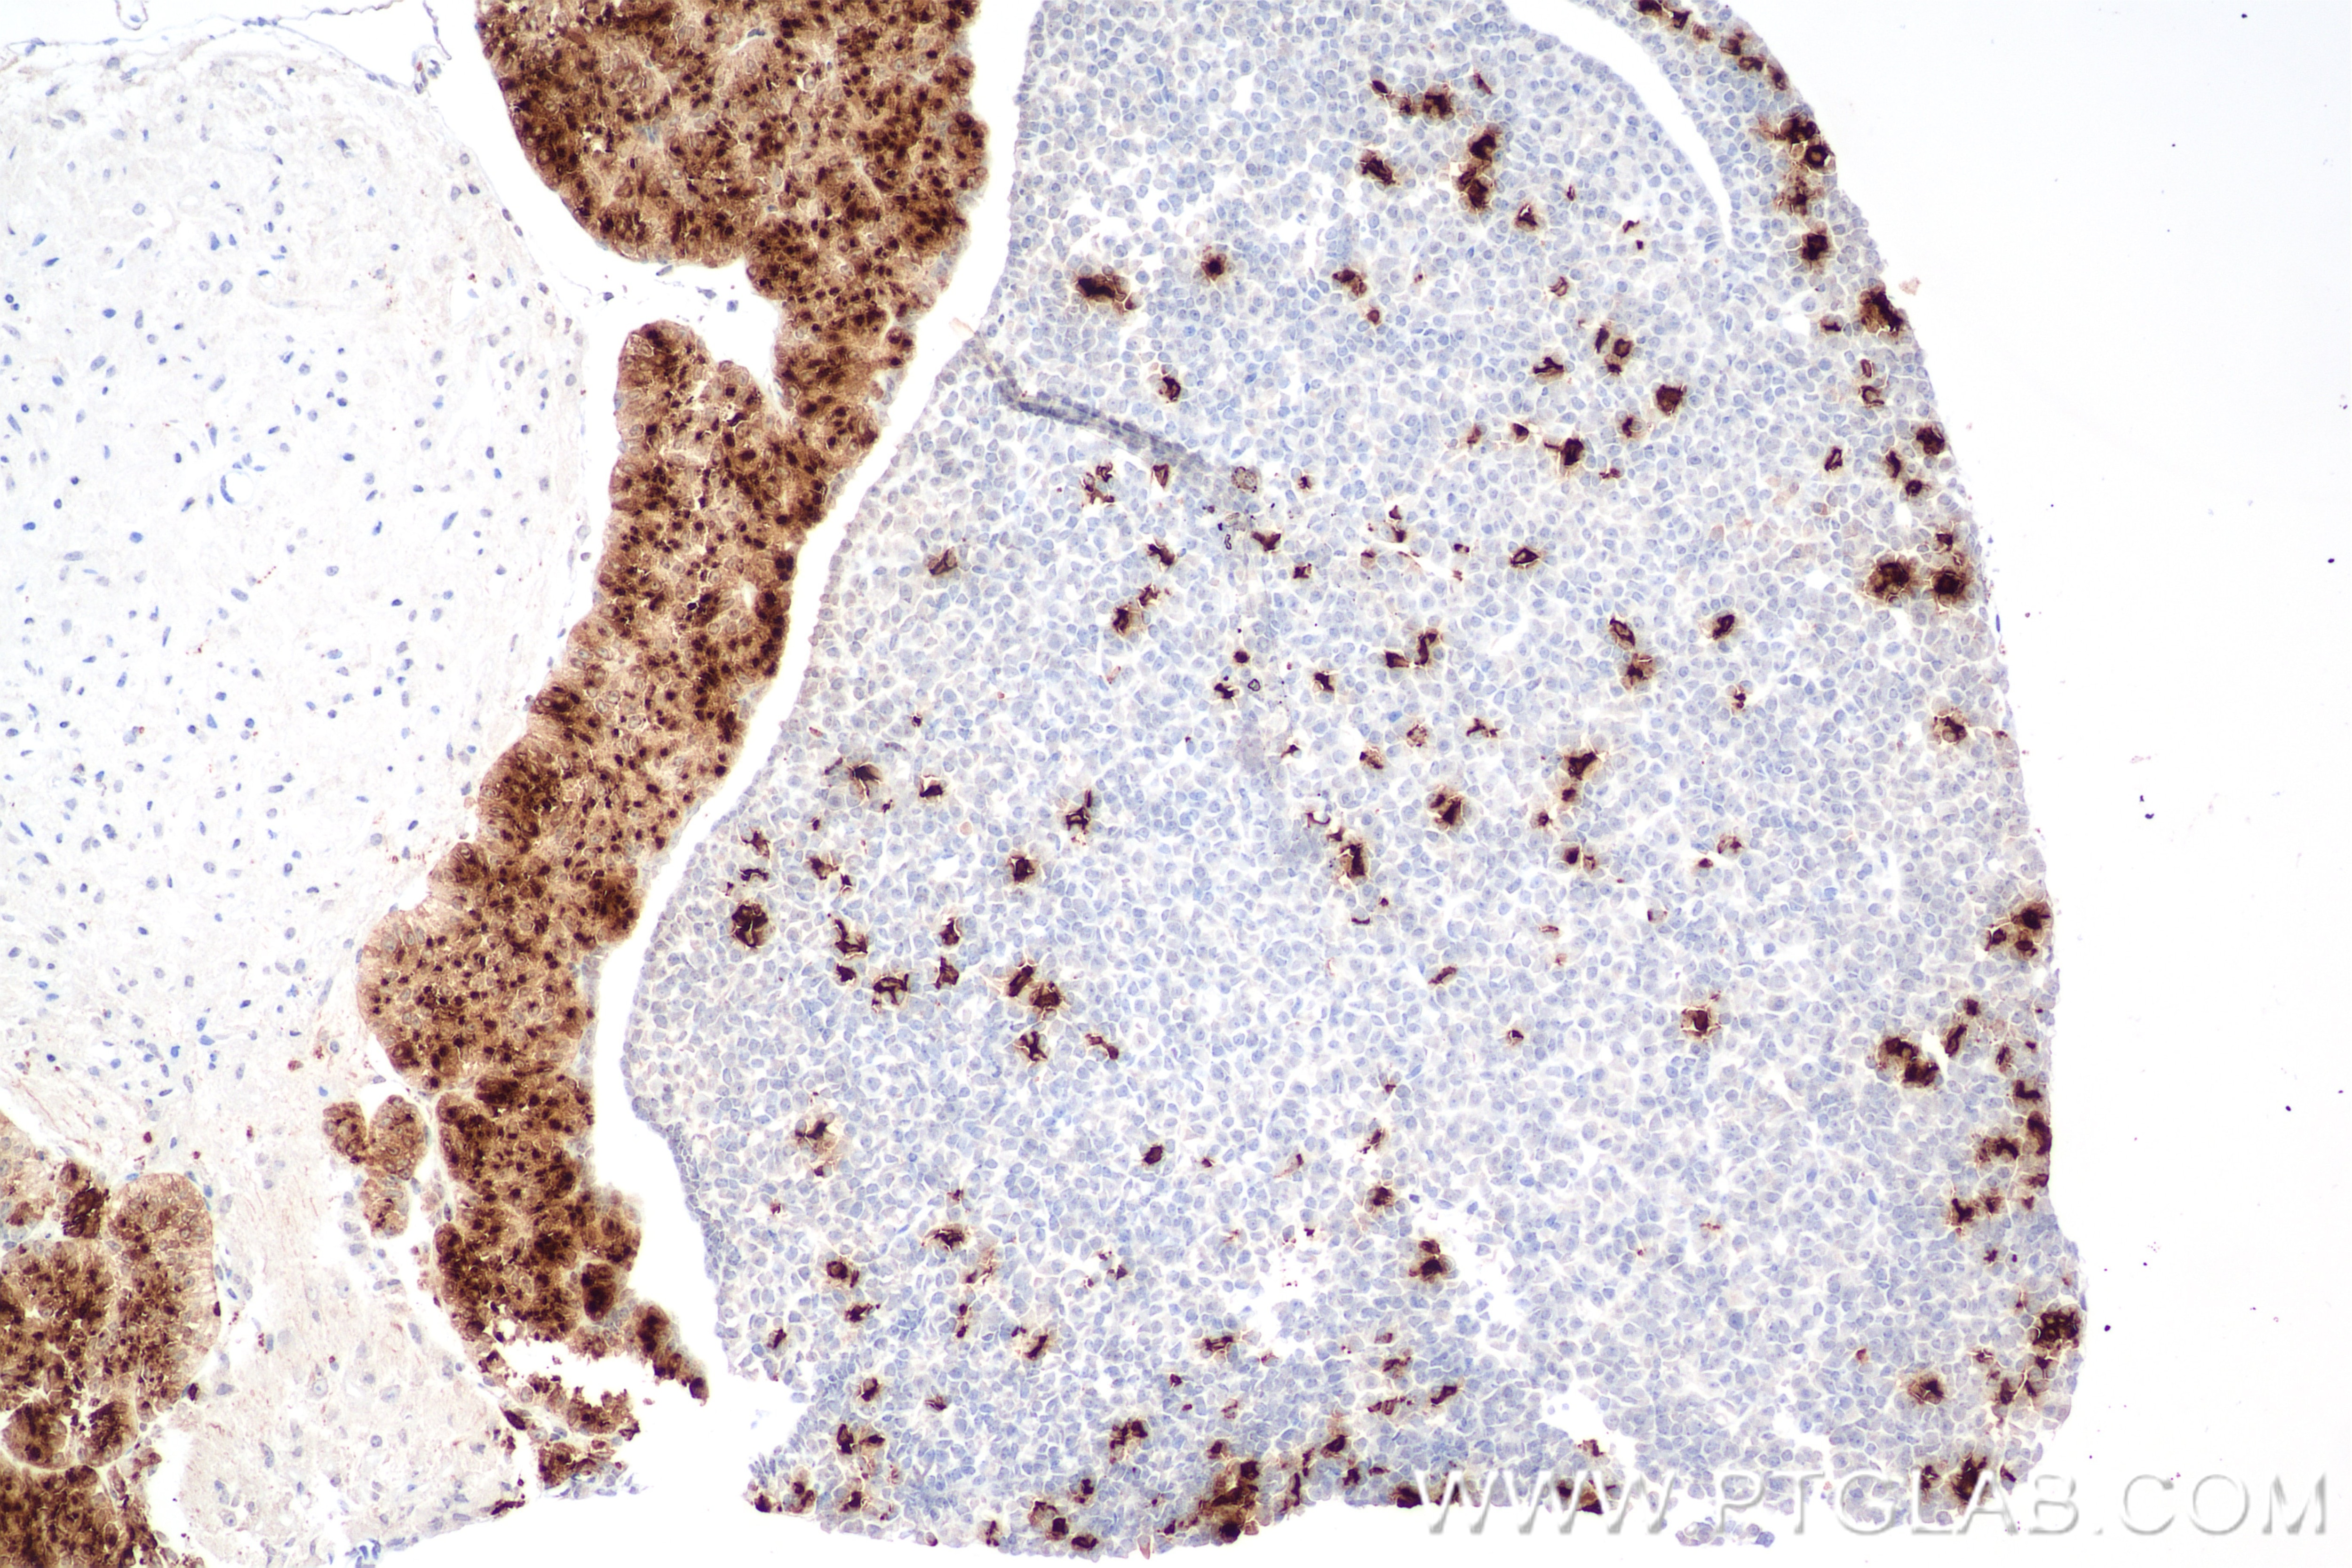

| Positive IHC detected in | mouse pituitary gland tissue Note: suggested antigen retrieval with TE buffer pH 9.0; (*) Alternatively, antigen retrieval may be performed with citrate buffer pH 6.0 |

82498-2-RR targets ACTH in IHC, IF-P, ELISA applications and shows reactivity with human, mouse samples.